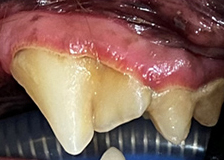

스케일링 전후 사진

스케일링 전

스케일링 후